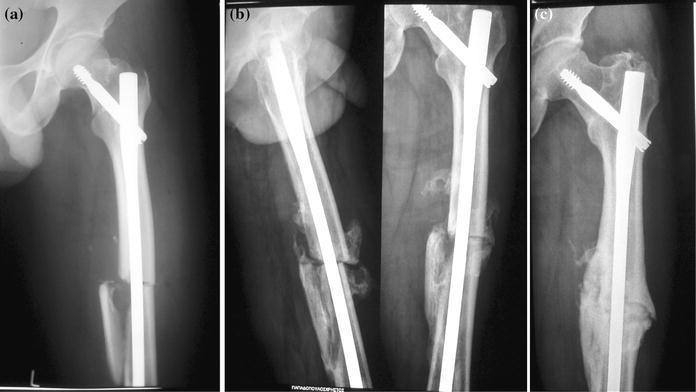

There were two cases of shaft fracture non-union. In the first case, the fracture was originally fixed in distraction, which ultimately led to the breakage of the distal locking screws and valgus displacement of the shaft fracture at 5 months after surgery (Fig. 2). Revision surgery was performed to correct the deformity. The broken screws were replaced, and iliac autograft was used to induce union. A hypertrophic non-union of the shaft fracture occurred in the second case, which was treated by exchange nailing and bone grafting. In both cases, satisfactory union occurred 6 months after additional surgery (Fig. 3). There was one case of peroneal nerve palsy that presented immediately after surgery, presumed due to excessive traction during fracture reduction manoeuvres. At the final follow-up, the patient had grade 3 ankle extensor strength (Medical Research Council classification) and reported occasional difficulty to perform pre-injury everyday activities. Heterotopic ossification at the tip of the greater trochanter was radiographically evident in two cases without causing any functional deficit.

Fig. 3.

Radiographs showing ipsilateral neck and shaft fracture (patient No 4): a originally treated with intra-medullary nailing, b hypertrophic non-union occurring 5 months post-operatively and c satisfactory union achieved after exchange nailing and bone grafting